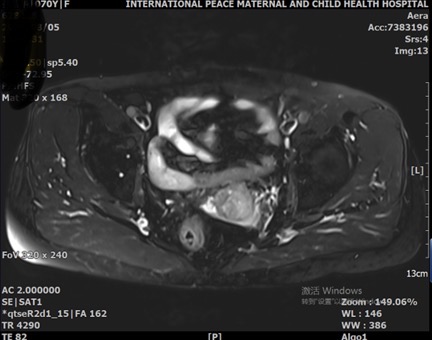

8月5日中国福利会国际和平妇幼保健院就诊,阴道镜检查:宫颈7-12点见组织糟脆肿物,约1.5cm,糟脆组织延伸至宫颈管内;活检病理:(宫颈肿物)鳞形细胞癌,未见明确脉管内瘤栓,组织表浅,浸润深度无法估计。肿瘤指标:SCC:14.1ng/ml。盆腔MR增强:宫颈占位(范围约24mm*24mm*44mm),累及宫颈全层及阴道前壁上1/3。